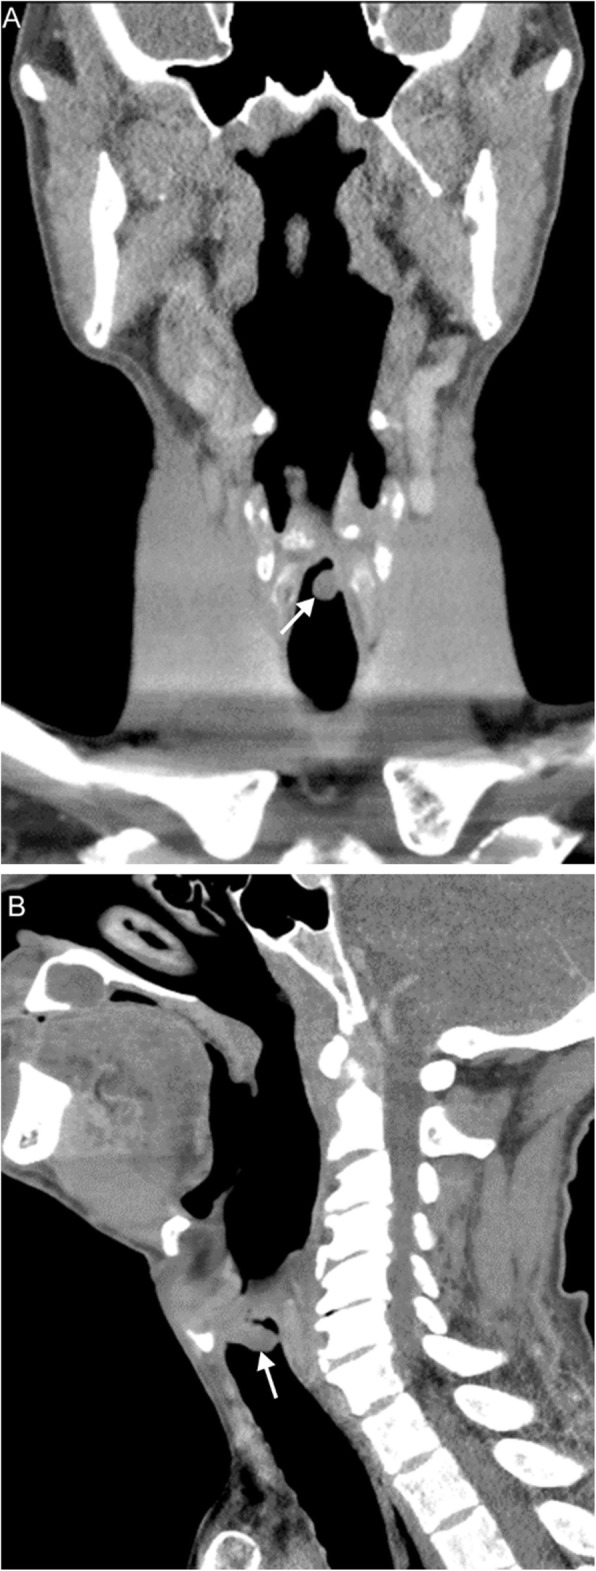

Fig. 4.

Laryngocele. A 67-year-old man with history of prior tongue base and oropharyngeal squamous cell carcinoma status post radiation completed 8 years prior presents with dysphagia and hoarse voice. Axial (a) and coronal (b) contrast-enhanced CT images demonstrate bilateral supraglottic laryngoceles (arrows) with mild extralaryngeal extension on the left